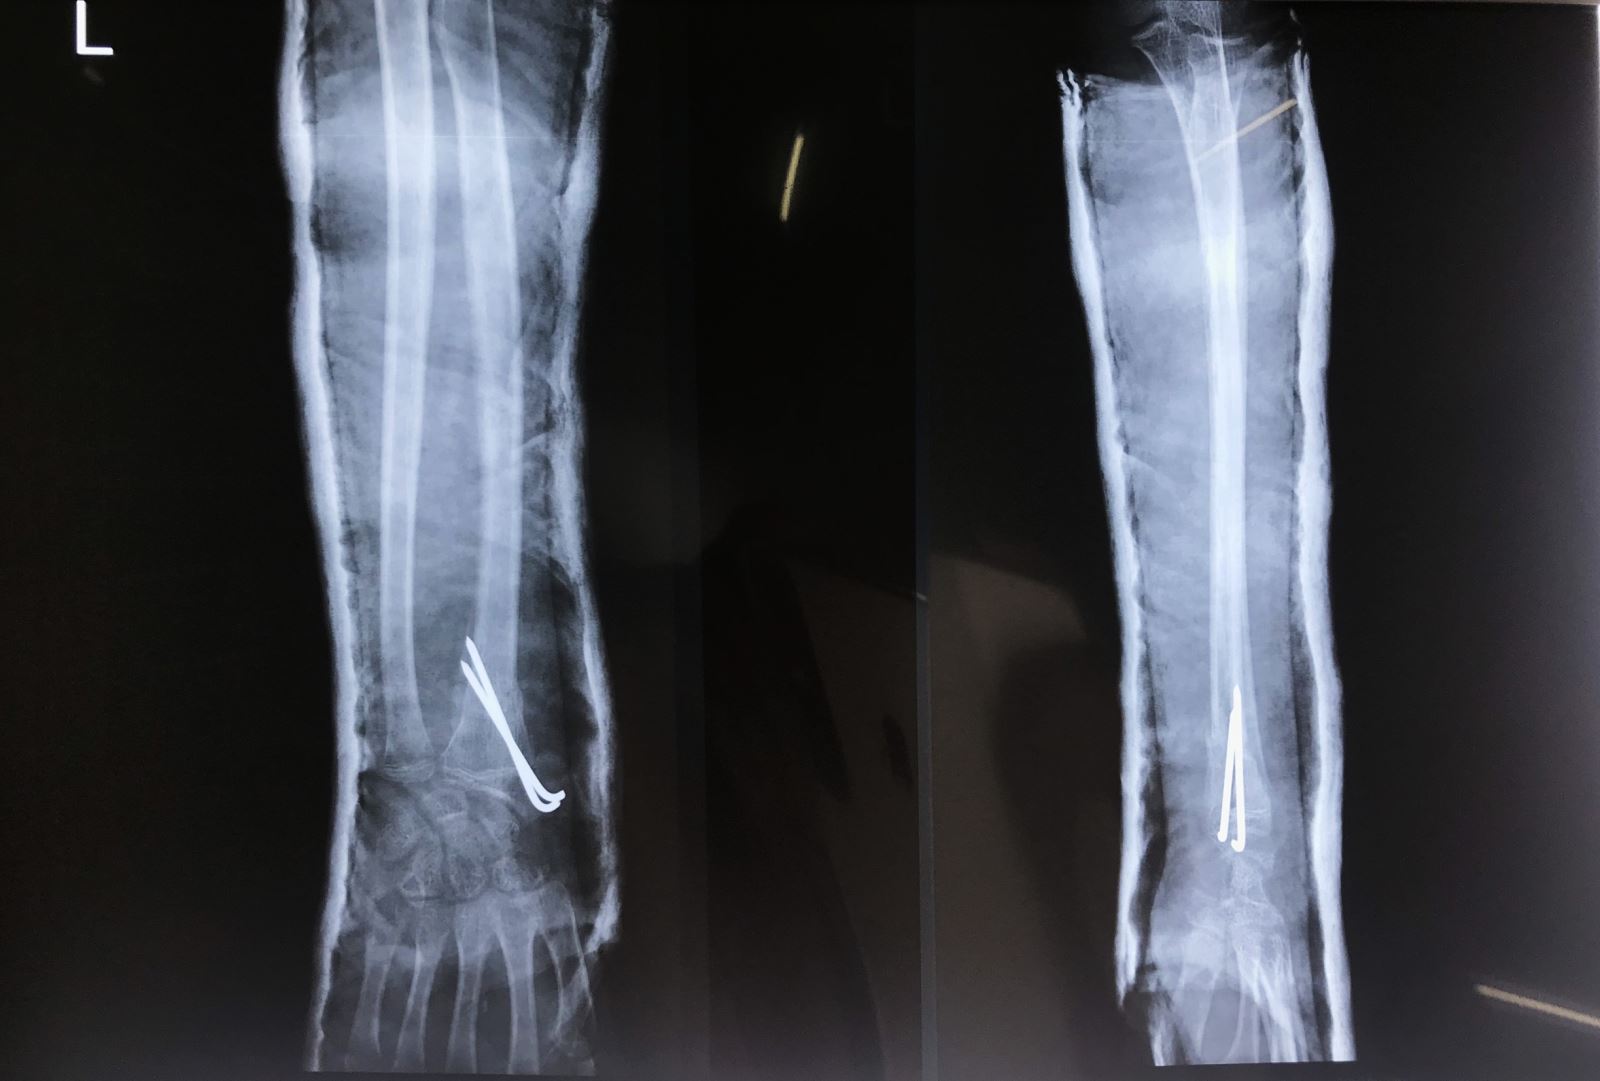

2. Phẫu thuật

1. Nắn kín và xuyên đinh qua da dưới màn hình tăng sáng

2. Mổ hở nắn chỉnh và cố định bên trong: Nắn kín thất bại